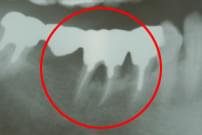

64歳 男性

左下7番が重度の骨欠損。

左下7番を抜歯、根面をクリーニングし、エムドゲインを塗布した後再植。